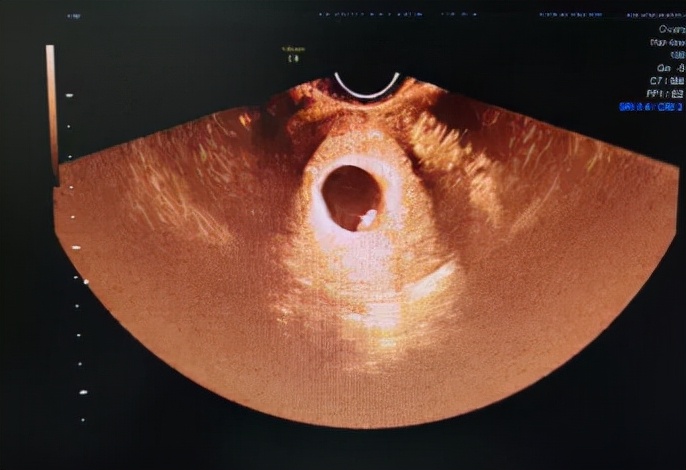

主要检查是不是宫内孕,是不是双胞胎,有没有胎心,胚芽长度。这样做主要为建档提供一定参考数据,需准妈妈憋尿进行腹部B超检查或者是阴道彩超检查。

第2次:11-13周,主要测量胎儿NT值

NT检查,最佳的检查时间为怀孕11周~13周+6天;